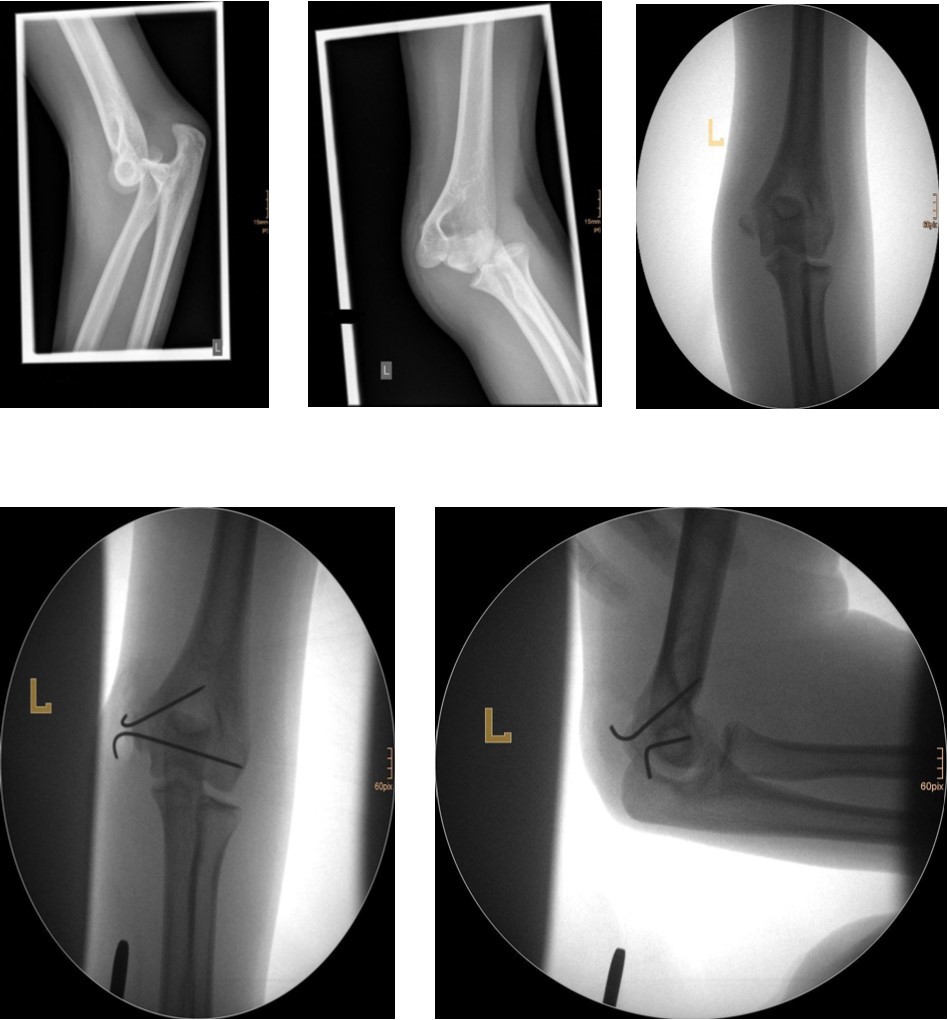

Non-displaced and stable fractures may be treated by cast immobilization with close follow-up, but fractures displaced >2 to 3 mm may indicate surgical fixation 7, 8. Surgical treatment can be done either by closed reduction and percutaneous osteosynthesis or open reduction and osteosynthesis. Figure 3.

Figure 3.9 year old male patient with a elbow dislocation and a dislocated left lateral condyle fracture which was treated by open reduction and osteosynthesis with a screw (personal collection)

Surgical fixation is either by screw, smooth K-wires or both. The K-wires can be buried under the skin or not.

The fracture fragment can be approached by a posteromedial incision that allows good exposure of both the fracture site and the ulnar nerve. Fixation is easily achieved with smooth K-wires or with screws in older adolescents. Two wires are necessary because of the sagittal rotation forces exerted on the fracture fragment by the common flexor muscles. Figure 4 and Figure 5.

Figure 4.14 year old female patient with a elbow dislocation and a dislocated left epicondyle fracture which was treated by open reduction and osteosynthesis with two divergent Kirschner wires (personal collection)

Figure 5.9 year old female patient with a elbow dislocation and a dislocated right medial condyle fracture which was treated by open reduction and osteosynthesis with a screw (personal collection)